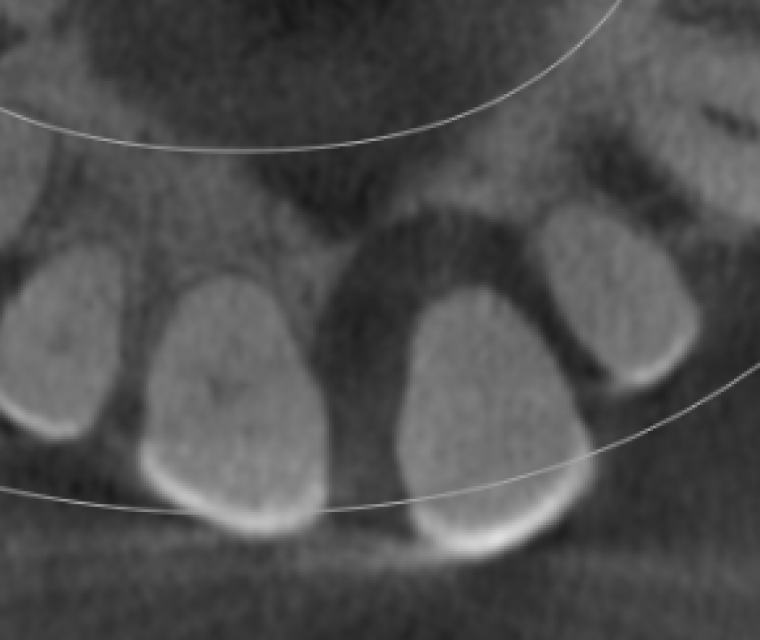

Schropp et al., 2003 reported that 50% of the ridge width is lost during the first 3 months after tooth extraction. In the second half of the lecture, we will touch on how to maintain a good soft tissue profile with socket preservation procedures that maintain both hard and soft tissue volume. Participants will learn how to prepare surgical sites for easy implant placements.

Schropp et al., 2003 reported that 50% of the ridge width is lost during the first 3 months after tooth extraction. In the second half of the lecture, we will touch on how to maintain a good soft tissue profile with socket preservation procedures that maintain both hard and soft tissue volume. Participants will learn how to prepare surgical sites for easy implant placements.

Surgical Site Preparation Process

Socket Preservation for implant

Surgical Site Preparation Process

Socket Preservation for implant